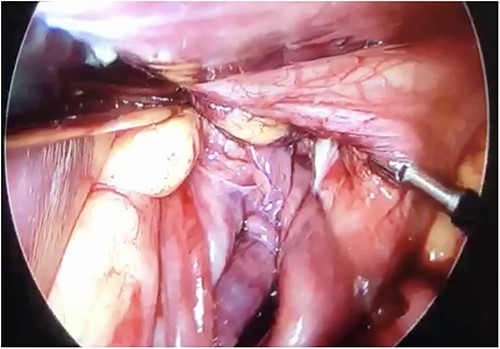

Initial treatment included intravenous crystalloid fluid repositioning, pain management, and antibiotic therapy. After diagnosing perforated gastric volvulus on a computed tomography (CT) scan, a diagnostic laparoscopy was performed. A hiatal hernia was identified with protrusion and twisting of the gastric body (Fig. 2). As the stomach body was reduced back to the abdominal cavity, a 1.5-cm perforation at the level of the greater curvature was detected. It was primarily sutured and covered with an omental patch (Fig. 3). The ischemic hernia sac containing the stomach was filled with food scraps and resected (Fig. 4). Laparotomy conversion was necessary due to hemodynamic instability attributable to the laparoscopic pneumoperitoneum. A 180° anterior fundoplication of the stomach (Dor’s Technic) associated with diaphragmatic raffia was performed. Gastric air leak testing was negative and intraoperative endoscopy showed no other defects on the gastric wall.

Laparoscopic view demonstrating an approximately 1.5-cm lesion at the level of the greater curvature of the stomach.